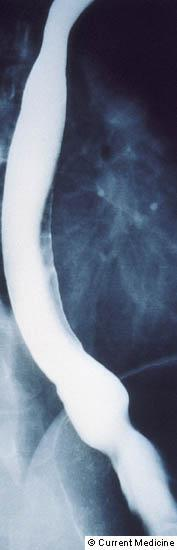

Diaqnozun dəiqiləşdirilməsi üçün kontrastlı Rentgenoloji müayinələr, KT və çox ehtiyatla endoskopiya edilir.

- Kontrastlı Rh-qrafiya - diaqnozu dəqiqləşdirən müayinədir.

- Rentgenoqrafik divertikul görünməsi

Xəstəliyin dəqiqləşdirilməsi üçün kontrastlı Rentgenoloji müayinə, KT və çox ehtiyatla endskopiya edilməlidir.

- Kontrastlı rentgenoqrafiya - dəqiqləşdirici müayinə üsuludur.

- Kontrastlı Rh-qrafiya - dəqiqləşdirici müayinə üsuludur.

Görüntlüləmə əlamətləri hansılardır?

Kontrast məhlulunn divertikul nahiyəsində toplanması

Kontrast məhlulun divertikul nahiyəsində toplanması

Görüntlüləmə əlamətləri hansıdır?